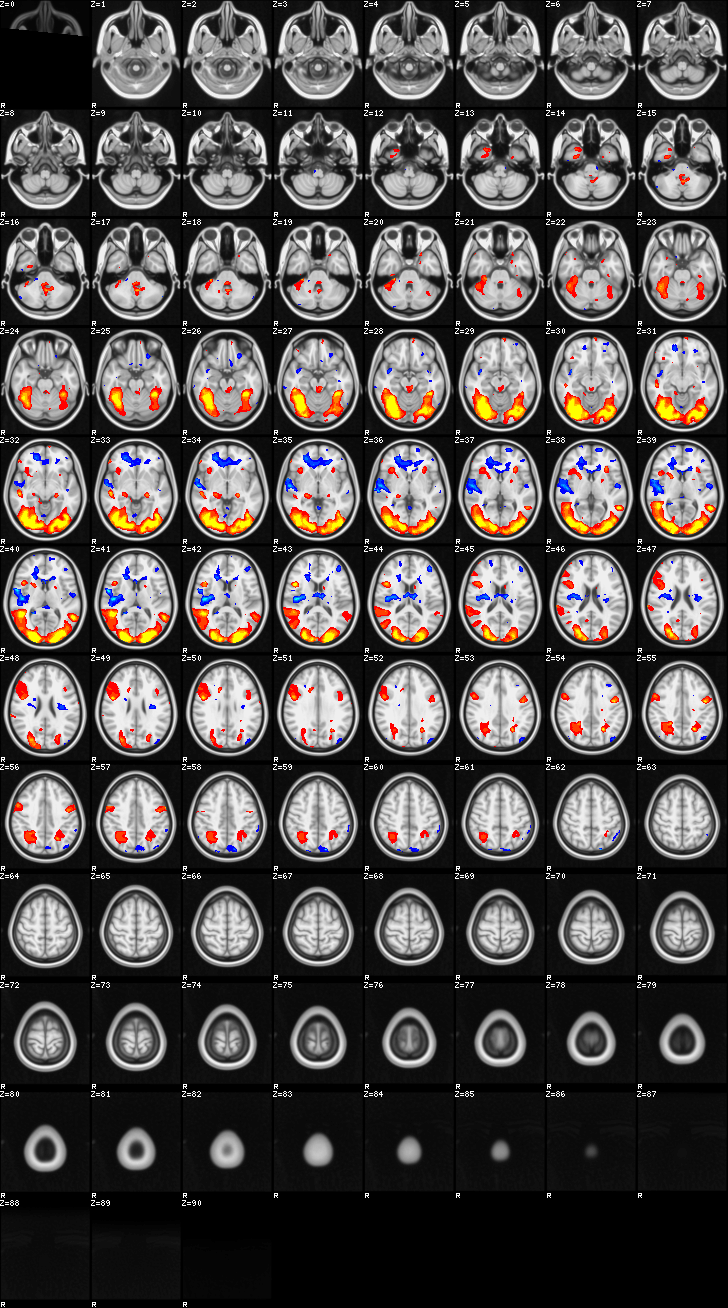

Mixed Effect (flame1)¶

ATM it is 8 subjects, 8 mm FWHM spatial smoothing, preliminary results only

Images thresholded abs value > 2.3 and colormap goes from 2.3 to 5 (red->yellow) or -2.3 to -5 (blue->lightblue)

Contrasts:

- FgtC

- Familiar > Control

- FltC

- Well – the opposite, and since both sides are plotted, it is just inverted colormap

- MOTOR

- Although based on the subject responses, since they occurred only during oddball, it reflects both oddball and motor reaction